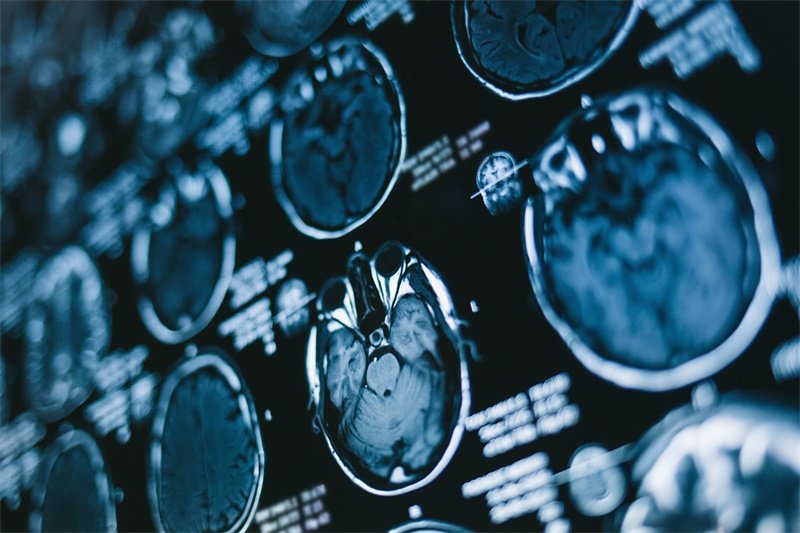

影像学检查

影像学检查是确诊脑积水的重要手段,通常包括计算机断层扫描(CT)和磁共振成像(MRI)。这些检查能够帮助医生观察脑室是否扩张及脑脊液的分布情况,从而判断是否存在脑积水以及其可能的成因。